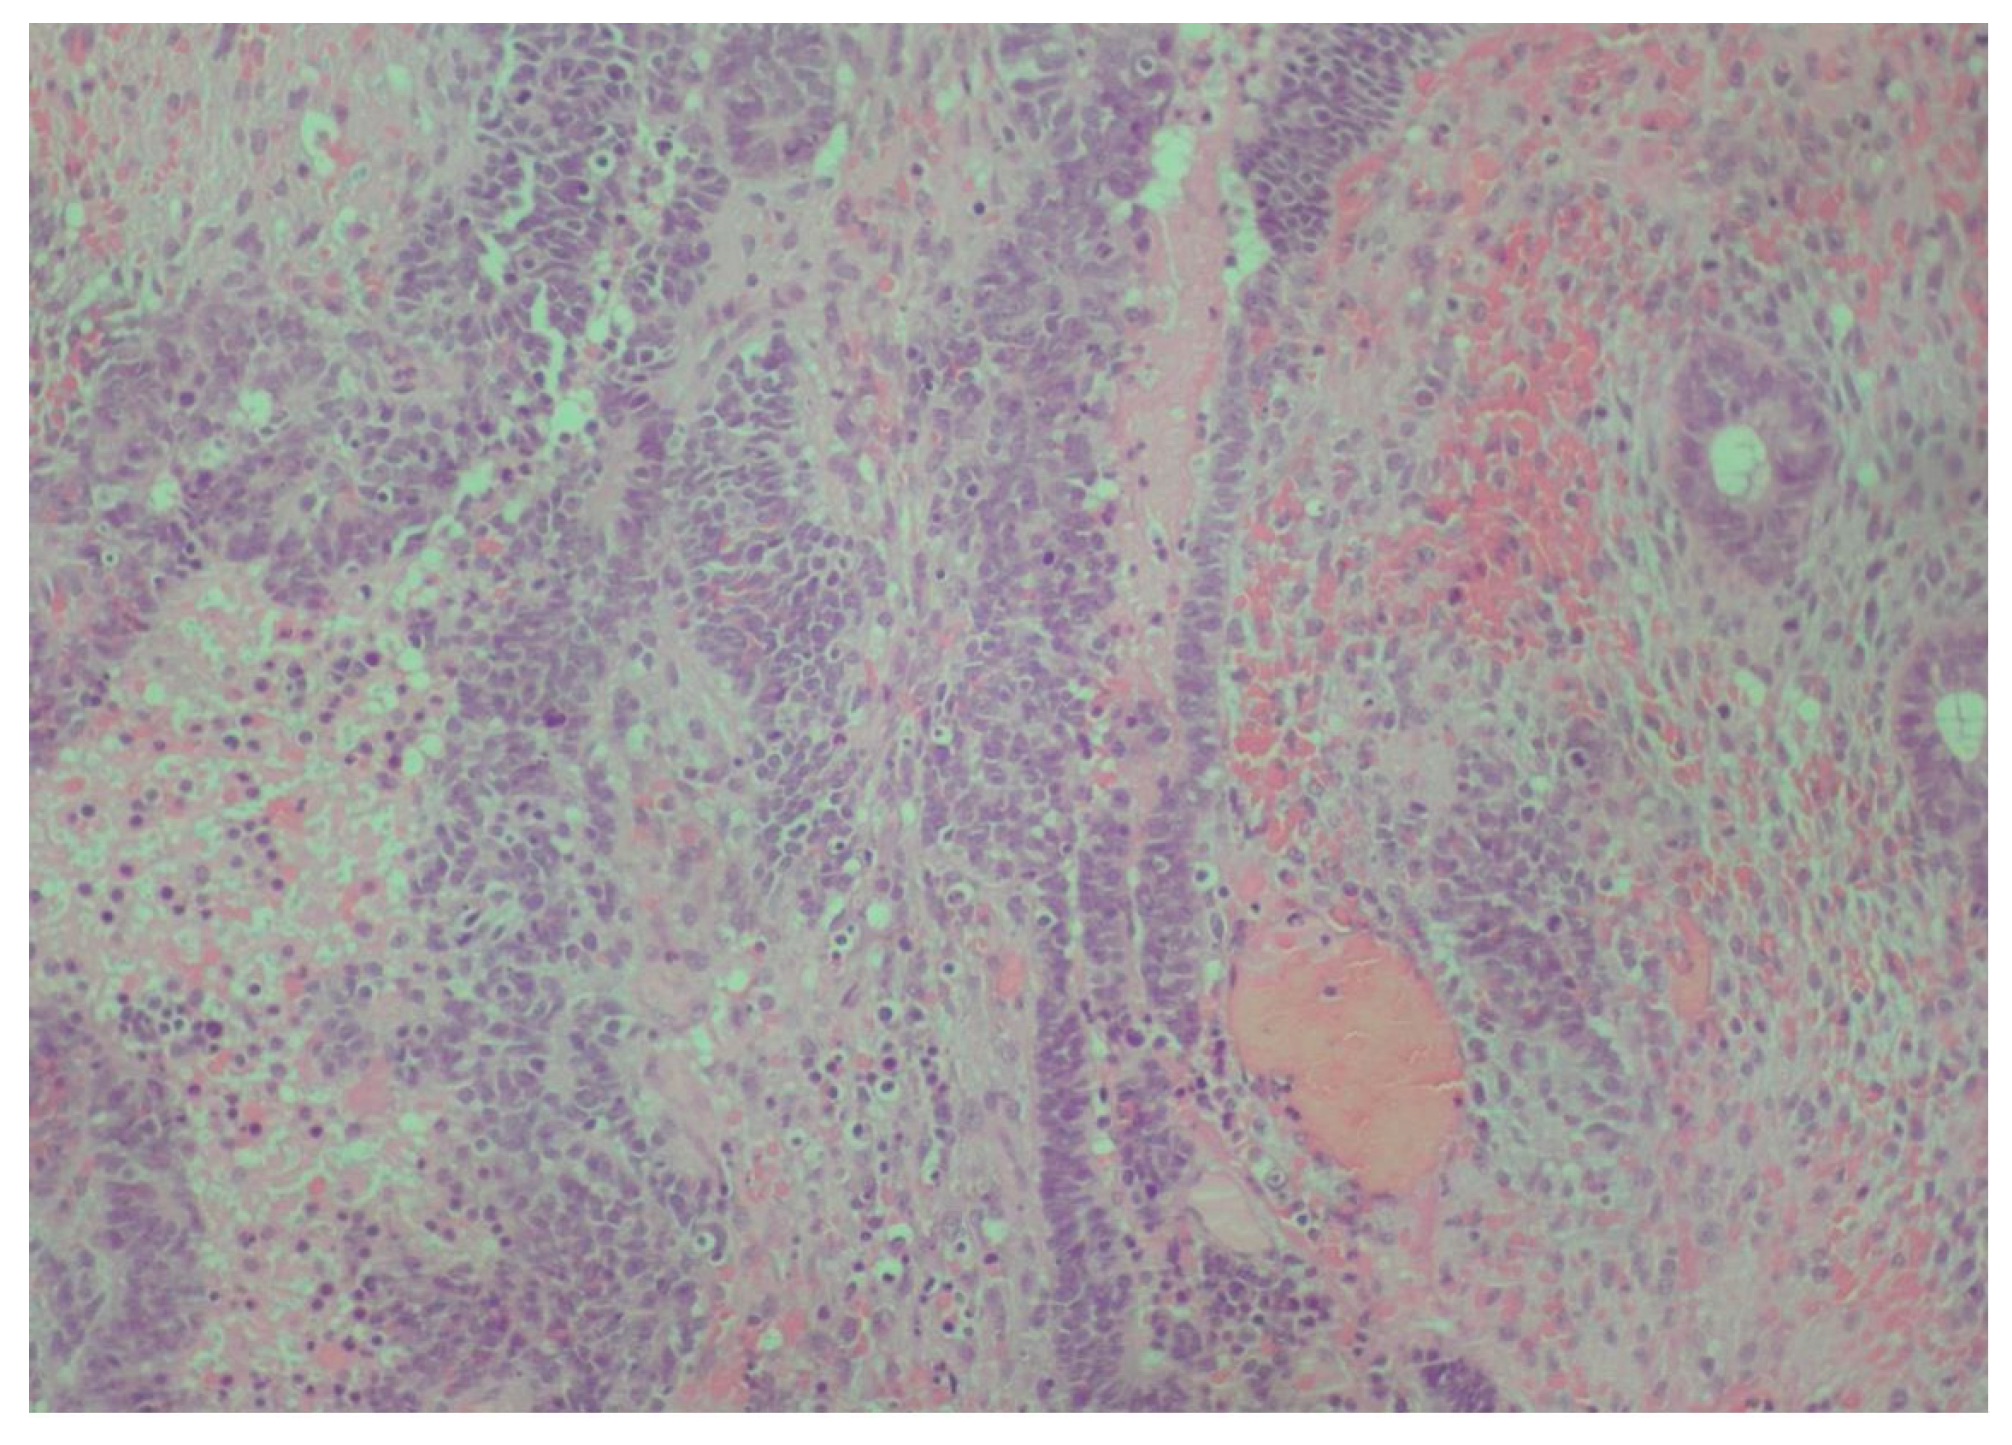

2. Case Presentation